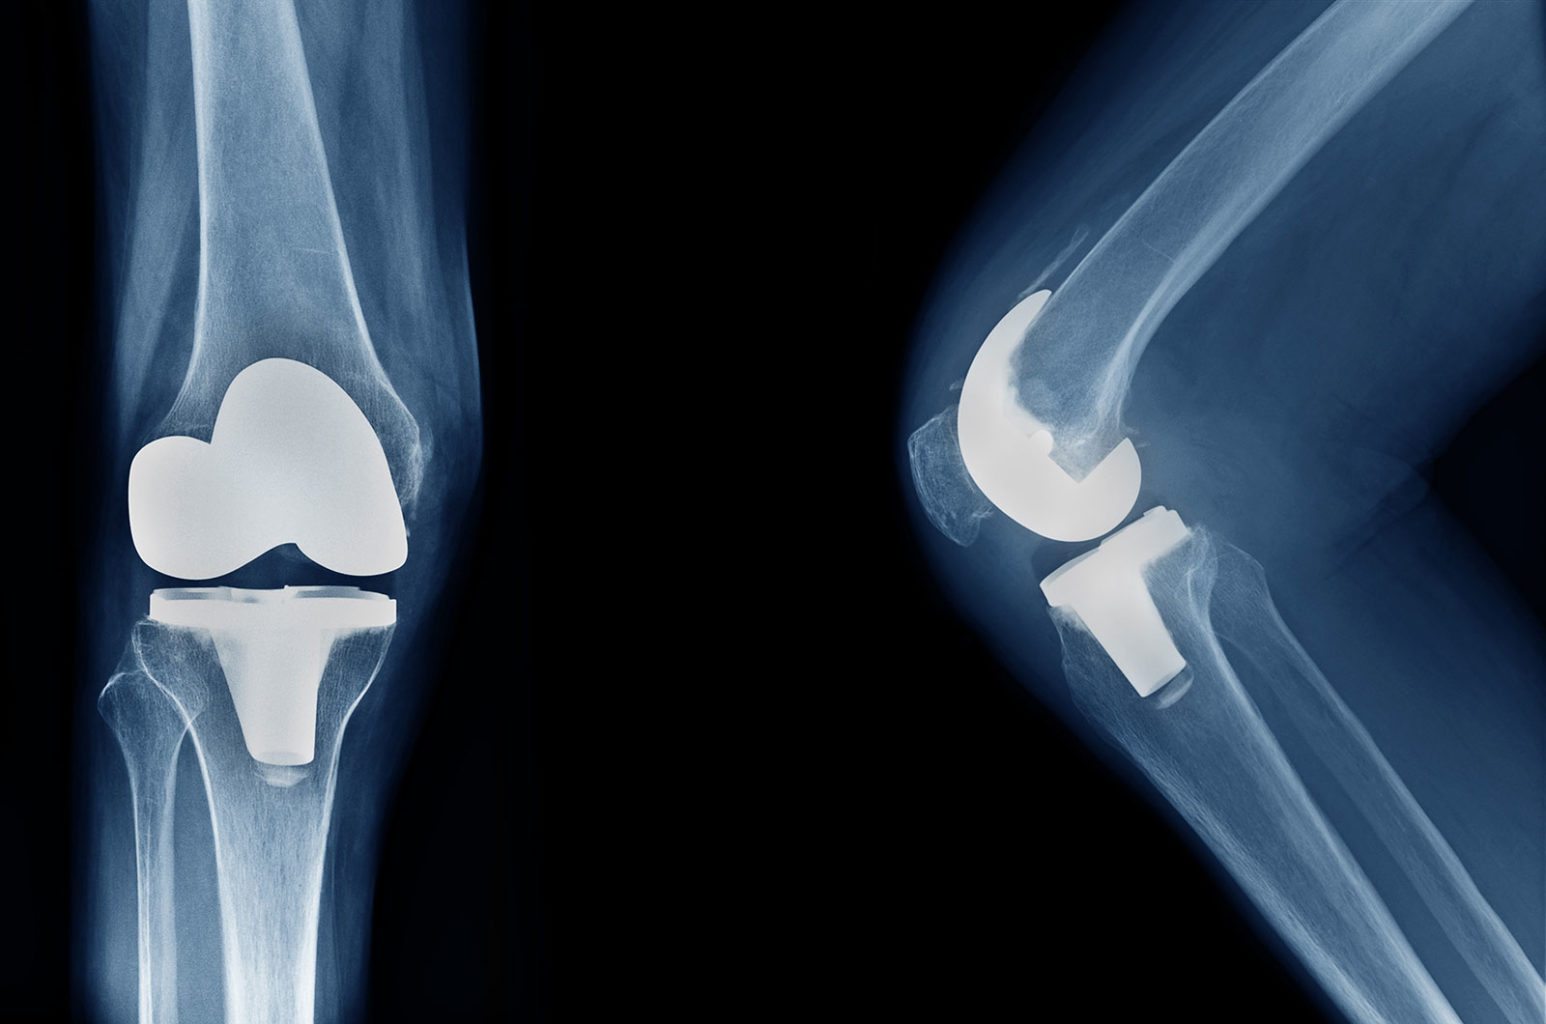

Knee replacement surgery has the potential to turn back the clock for people suffering from severe joint pain that limits their mobility and makes it hard for them to complete daily tasks. While surgery can’t return people to the same level of comfort and function they had before they developed arthritis, it can make them feel much less disabled.